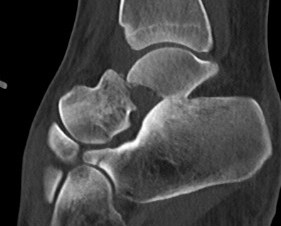

Xray / CT

Ensure no displacement / malalignment

Xrays

| AP | Lateral | Canale View |

|---|---|---|

| Entry point of the screws |

Evaluate neck reduction

|

Evaluates the neck reduction |

Lateral off articular surface Medial through articular cartilage |

Depth of screws |

Beam angled 75o to foot Foot 15o pronated |